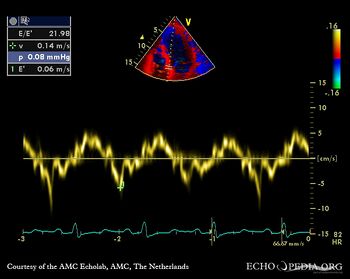

| HCM, diastolic dysfunction

| Courtesy of: AMC Echolab, AMC, The Netherlands

| TDI